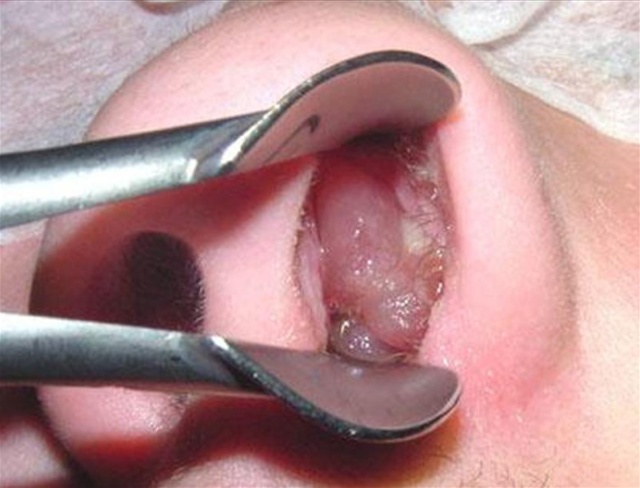

Mổ polyp mũi là một thủ thuật phổ biến để điều trị các polyp gây tắc nghẽn xoang và làm giảm các triệu chứng khó chịu như nghẹt mũi, đau đầu, mất khứu giác. Tuy nhiên, một câu hỏi mà nhiều bệnh nhân quan tâm là "Mổ polyp mũi có đau không?". Bài viết này sẽ giúp bạn tìm hiểu về mức độ đau khi mổ polyp mũi, cũng như cách chăm sóc bệnh nhân sau mổ polyp mũi.

Polyp mũi là những tế bào lớn hình nón hoặc hình trụ phát triển từ niêm mạc của mũi hoặc xoang mũi. Khi polyp mũi gây ra các triệu chứng như khó thở, tắc nghẽn mũi, và ảnh hưởng đến chất lượng cuộc sống, bác sĩ có thể quyết định thực hiện ca mổ để loại bỏ chúng. Ca mổ polyp mũi nhằm mục đích loại bỏ polyp mũi.